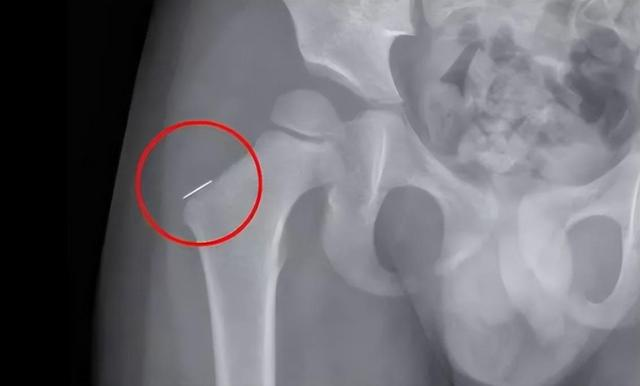

Sự việc chỉ được phát hiện sau khi họ Dương đã rời khỏi nhà của vợ chồng anh Trương. Vì con trai liên tục khóc lớn, vợ chồng anh đưa đi khám thì không tìm ra nguyên do. Vợ chồng anh Trương nghe tới đây không khỏi điếng người.